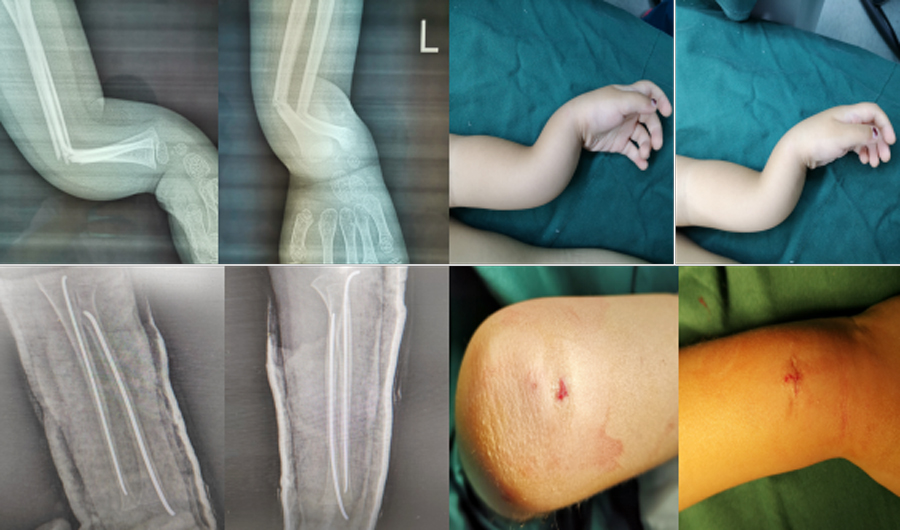

微创治疗骨折,手术切口小,损伤小,恢复快。